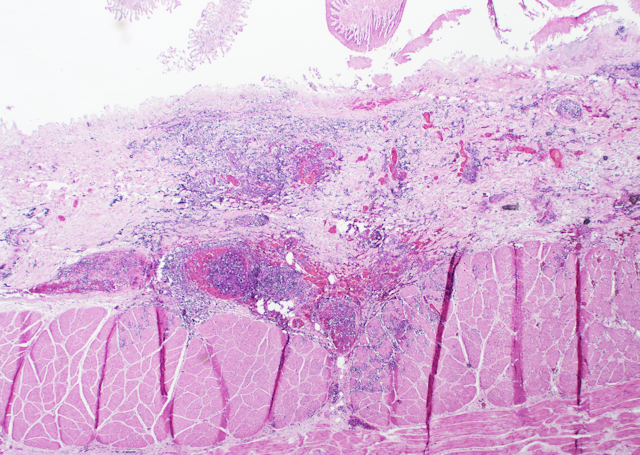

Als Hauptbefunde bei der Obduktion wurden im Pansen zahlreiche bis zu 6 cm große runde Entzündungsherde, die teilweise durch alle Wandschichten reichten und Entzündungen im anliegenden Netz verursachten, vorgefunden (Bild 1, 2 und 3). Der Pansen war mit Raufutter und sehr viel Getreide gefüllt. Dieser Inhalt roch relativ stark vergoren. Labmagen und Darm wiesen eine katarrhalische Entzündung auf.

Bild 1: Durch die Wand des Pansens bis in das Netz reichende rundliche Entzündungsherde

In der feingeweblichen Untersuchung wurde festgestellt, dass es sich bei den herdförmigen Veränderungen in der Wand des Pansens um Infarkte handelte, in denen zahlreiche Schimmelpilzhyphen nachgewiesen werden konnten (Bild 4 und 5).

Bild 4: Tiefreichende Entzündung der Pansenschleimhaut mit Entzündung der Blutgefäße, HE-Färbung, 20fache Vergrößerung